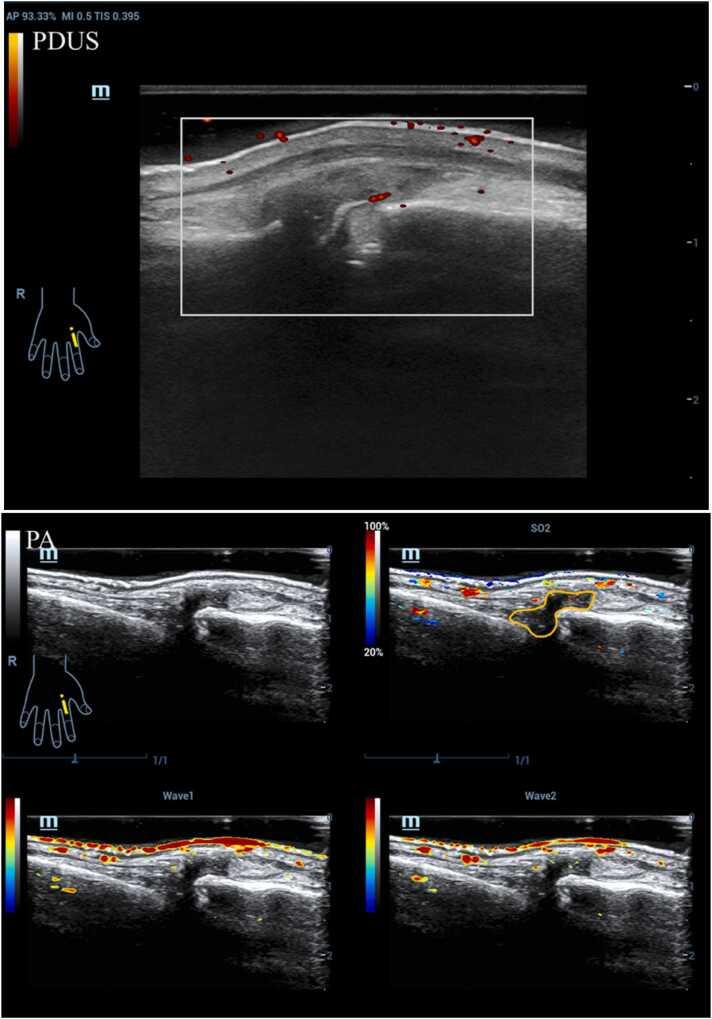

In this study, we recruited 111 patients diagnosed with RA and conducted examinations of seven small joints on their clinically dominant side using a PA/US imaging system. The PA and power Doppler ultrasound (PDUS) signals were semi-quantitatively assessed using a 0-3 grading system. The cumulative scores for PA and PDUS across these seven joints (PA-sum and PDUS-sum) were calculated. Relative oxygen saturation (So) values of inflamed joints on the clinically dominant side were measured, and categorized into four distinct PA+So patterns. The correlation between PA/US imaging scores and disease activity indices was systematically evaluated.

This study utilized multi-modal PA/US imaging to analyze Rheumatoid Arthritis (RA) patients' synovial tissues and affected joints. When juxtaposed with traditional PDUS imaging, the PA approach demonstrated enhanced sensitivity, especially concerning detecting small vessels in thickened synovium and inflamed tendon sheaths. Furthermore, correlations between the derived PA scores, PA+So patterns, and standard clinical RA scores were observed. These findings suggest that multi-modal PA/US imaging could be a valuable tool in the comprehensive assessment of RA, offering insights not only into disease activity but also into the oxygenation status of synovial tissues. However, as promising as these results are, further investigations, especially in larger and diverse patient populations, are imperative.